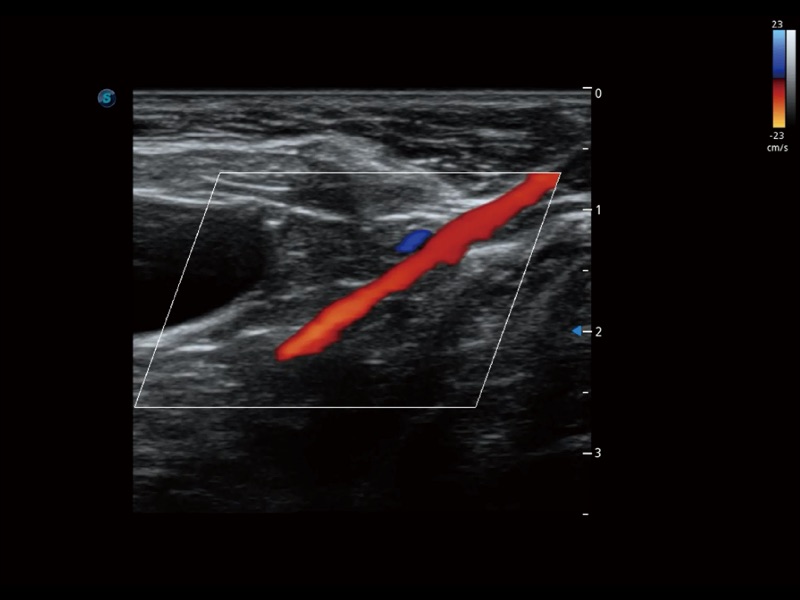

(犬)髂动脉血流

• 宽景成像

通过色彩血流和实时宽景相结合,可观察到完整的静脉或动脉的血流,方便医生检查。实时扫查过程中,如有任何操作失误也可以很容易地进行回扫擦除,而不会中断扫查。